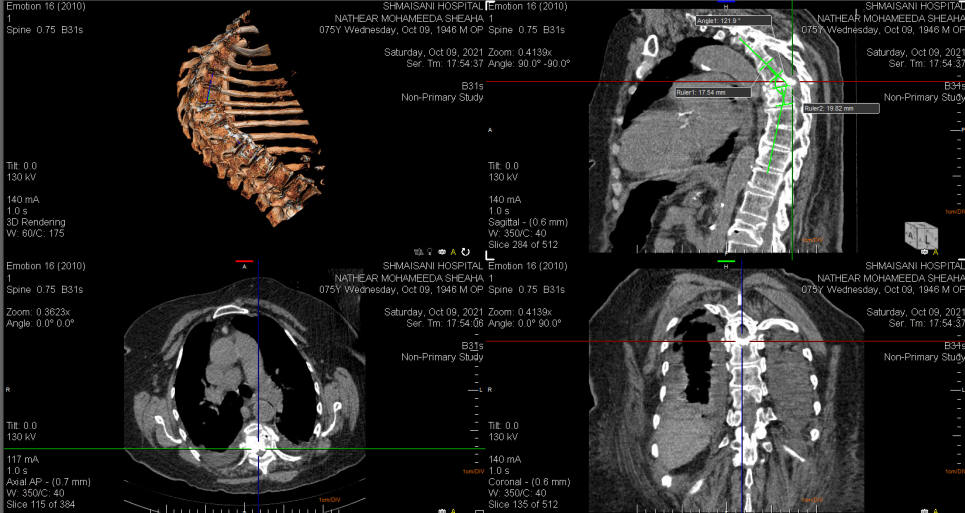

11-OCTOBER-2021  NAZAR MUHAMED SALAM  74 YEARS  INFECTIOUS DESTRUCTION OF D6 WITH THE POSTERIOR FRAGMENT SLIPPED TO THE CANAL AND COMPRESSING THE SPINAL CORD.

On examination, the patient in agonizing pain and cannot find position to alleviate the pain. Under G.A. the previously requested investigations showed complete destruction of the D6 body anterior 2/3 and the posterior third slipped to the vertebral canal compressing the spinal cord. There is hypalgesia below the nipples and weak proximal muscles both lower limbs. There is intrapleural collection both sides and ESR was 40 mm/h and CRP was 162 mg/L. Septic work up done showing staphylococcus coagulase negative (Oxacillin resistant). During stay in hospital she progressed bowel obstruction for what the general surgeons and proctologists with nephrologist were involved with the problem and proctoscopy done 2 days ago resolved the problem. Lab repeated the day before surgery showing decrease of CRP to 30 mg/L  and ESR down to 30 mm/h. CT-scan of the dorsal spine done 08-October showing the height of D5 and D7 are 19.5 mm. The D5-6 disc height is 2.3 mm and Cobs angle at the deformed D6 was 60 degrees.

With the patient in the left side position, using double lumen endotracheal tube, right sided thoracotomy was achieved between D5 and D6 ribs. The right lung was collapsed. Dissection of the anterior border of the D5, D6 and D7. It was difficult to dissect the sympathetic chain due to massive scar and a huge amount of intrapleural fluid came out. The right D7 rib was harvested for subsequent graft. Using the C-arm the level of D6 was identified and removal of the osteomylitic bone and the fluids was achieved and sent for CXS and histologic verification. Using ANTARES Medtronic system distraction of the affected area was achieved and the dissection was carried out until the dura was seen in the posterior aspect of the resected pathological parts. The resection was carried out so that the healthy endplates were seen at both sides. Using The vertespan thoracic extra small was inserted into the cavity and it was expanded to reach 26 mm in anterior height after filling it with bone graft obtained earlier from the rib. For achieving the proper stabilization the caudal and rostral plates were applied to the D5 and D7 bodies with CD HORIZON 6.5X 35 mm length for distracting and and stabilizing the construct. Cross connector 13 mm length was applied between the rods 5.5 mm width. Check by the C-arm from different angles showed acceptable reduction and fixation of the dorsal spine. Routine closure of the wound with under-water seal inserted to the right intrapleural space. Smooth postoperative recovery. She was sent to the ICU.